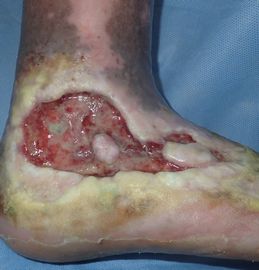

2000年ころから右下腿に傷ができて,次第に深くなった。〇〇大学附属病院皮膚科に通院し,2度皮膚移植を受けたが皮膚は生着しなかった。今年に入り,同院循環器科で診てもらったが,医師から「浸出液が悪い。これが傷の周りの皮膚を腐らせ,潰瘍が拡大している原因だ。浸出液を止めないといけない」と説明され,カデックス軟膏が処方され,傷口をカデックスを埋めるように指導された。

10月29日,当科受診。傷口を覆っていたカデックスを除去して洗浄し,「穴あきポリ袋+紙おむつ」(勝手に鳥谷部先生のサイトにリンク)で被覆。治療法を説明。

| 10月29日 |